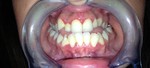

Paziente candidato a intervento di chirurgia Ortognatica

I risultati Arrivano e si vedono.

Uno dei nostri ultimi cambiamenti radicali.Il tuo sorriso può essere più vicino di quello che immagini